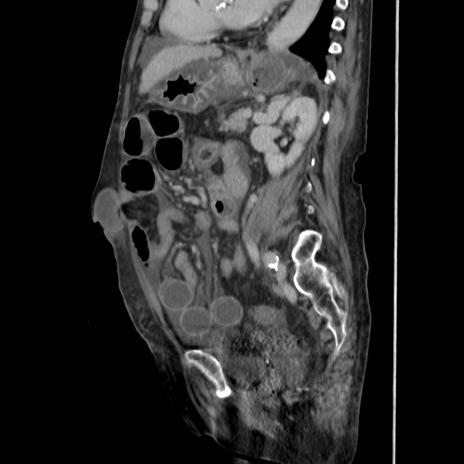

症例31(矢状断像)

【症例】80歳代 女性

【主訴】腹部膨満感

【現病歴】他院にて肝硬変にてフォロー中。1週間前から便秘、腹部膨満感、臍部腫瘤あり受診となる。

【既往歴】肝硬変

【身体所見】腹部膨隆あり、皮膚変化なし、疼痛なし。

【データ】WBC 4600、CRP 0.25